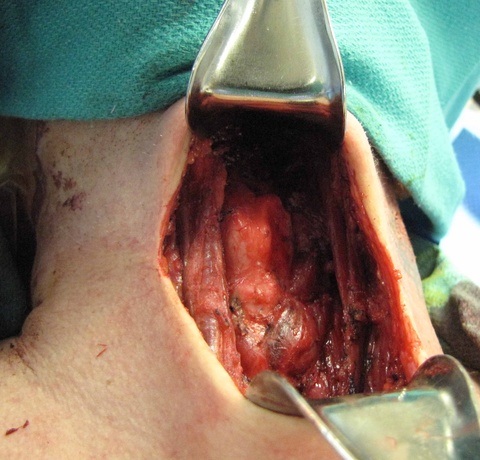

The patient was then prepped (including 1010 drape) and positioned for a central neck dissection thyroglossal duct cyst removal. Just to the left of midline, a large mass was palpated. A 15 blade was used to incise the skin with a horizontal marked incision and down onto the mass. Subplatysmal flaps were raised superiorly and inferiorly down to the area of the thyroid. We divided the straps midline. Of note just to the left of midline, the strap muscles were adherent to the cyst. Inferiorly the cricoid cartilage was identified as well as the thyroid. The mass was dissected around and it appeared to be in continuity with the pyraminal lobe and isthmus. The thyroid was divided to the right and then to the left and tied off with a 3-0 silk running stitch to permit resection of the isthmus in-continuity with the mass extending above.

We dissected the cyst and mass from an inferior to superior direction as it was removed from the cricothyroid muscles and thyroid cartilage up to the hyoid bone with care to avoid the superior laryngeal nerves. A small amount of strap musculateure was removed with the specimen where it was densely adherent on the left side.

The hyoid bone was identified with preservation of soft tissue about the central portion and isolation of the bone laterally. On the right side, just medial to the lesser cornua and used a Freer underneath to protect while we released the hyoid with the mighty bite. The left side was addressed in identical fashion, except that we were lateral to the lesser cornua. The dissection was carried superiorly with a cuff of muscle.